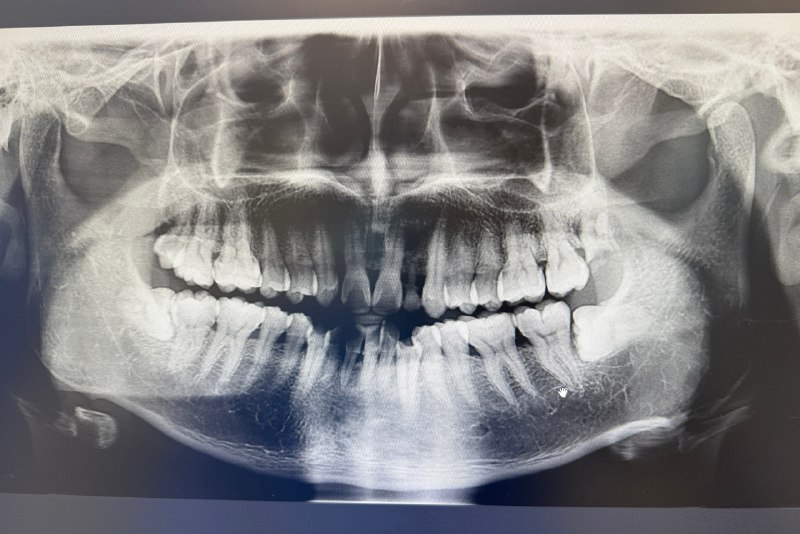

我的牙片

上图是我10月10日拍的牙片,4颗智齿全长出来了。医生看过后,说了两点:

● 左侧上方那颗,已经蛀掉了,得拔掉

● 下面2颗,大部分埋在牙龈中,会有些难拔